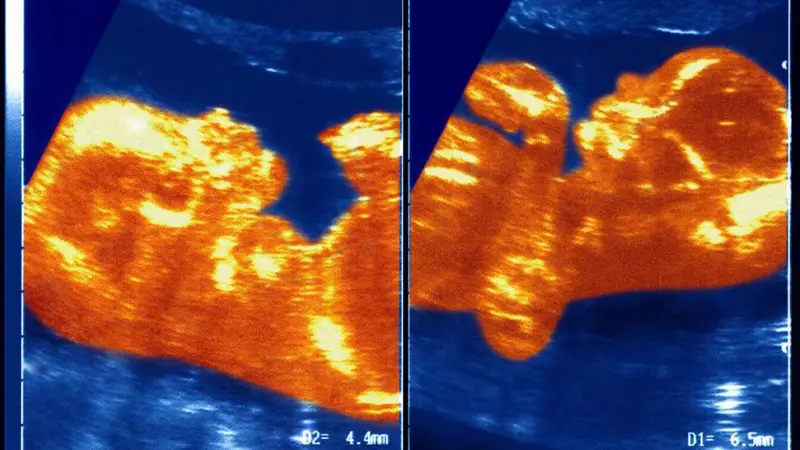

Imagem de ultrassonografia ilustrando o caso raro de quimerismo em gêmeos. (Foto: Instagram)